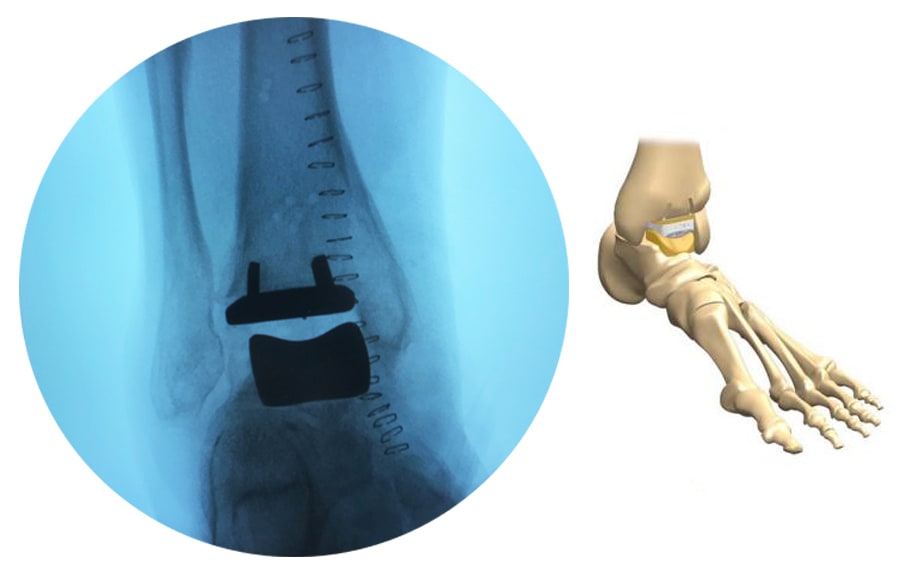

Пациент, обратился к специалистам в Многопрофильный республиканский медицинский центр с жалобами на боль в голеностопном суставе, от которой страдал на протяжении 10 лет. Он не смог смириться с мыслью о том, что сустав будет неподвижен, и, взвесив все, принял решение сохранить функцию голеностопного сустава. Рустам Фаттулоевич Каримов и Ислам Абдуллаевич Магомедов врачи-травматологи-ортопеды Центра заменили пациенту весь сустав на искусственный, который позволяет сохранить приличный объем движений.

Подобные операции выполняются пациентам при запущенном артрозе голеностопного сустава. На сегодняшний день, большинство медицинских центров предлагают провести лечение другим хирургическим методом – артродез голеностопного сустава, это полное замыкание сустава, то есть обездвиживание этой области. Поэтому, чтобы сохранить движение голеностопного сустава необходимо проводить только эндопротезирование, позволяющее продлить функцию поражённого сустава.